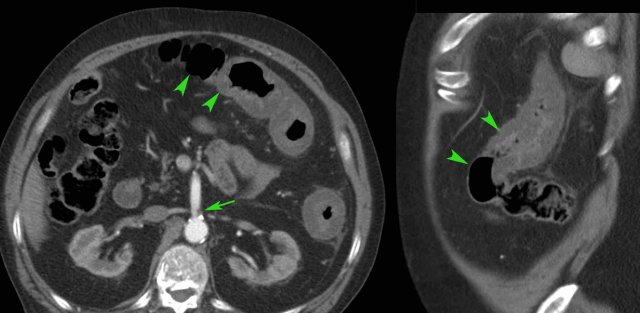

Right-sided infectious ileocolitis in a 33-year old man.

CT scan without contrast (history of severe allergy).

Prominent (sub)mucosal wall thickening of ileum and right colon.

Note also markedly enlarged mesenteric lymph nodes and normal appendix.